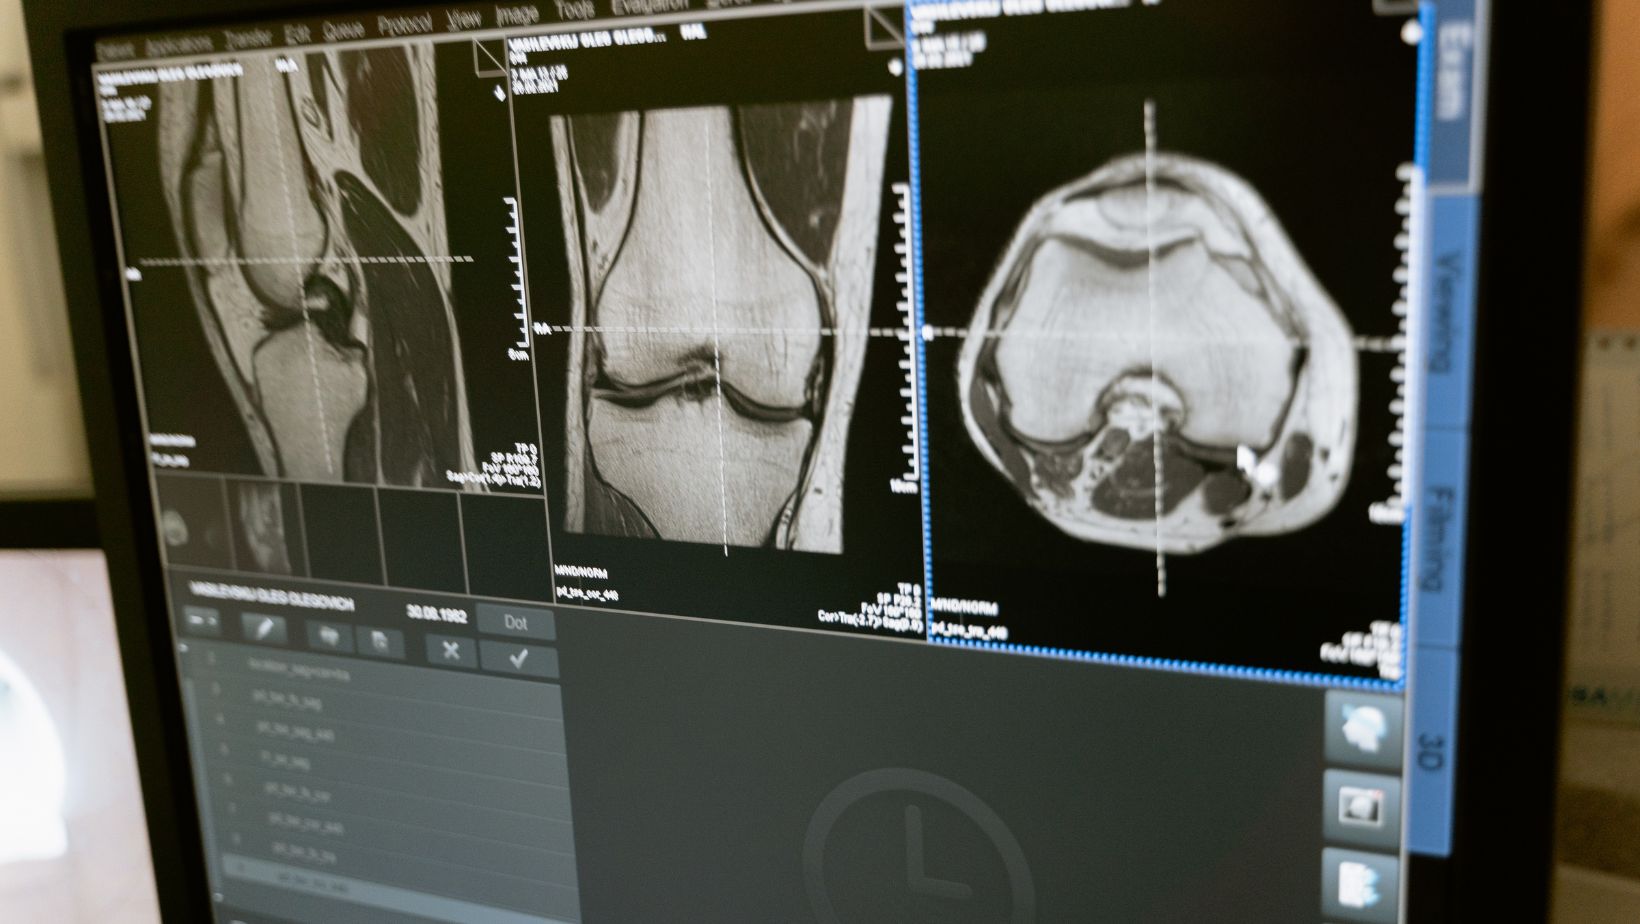

Dark Field Radiography’s potential to furnish us with detailed, nuanced image data takes chest radiography, MRI, and CT to a whole new level. Its promise lies not just in its enhanced detail, but also in its potential to redefine diagnostic proficiency, making it a promising prospect in the complex world of radiology.